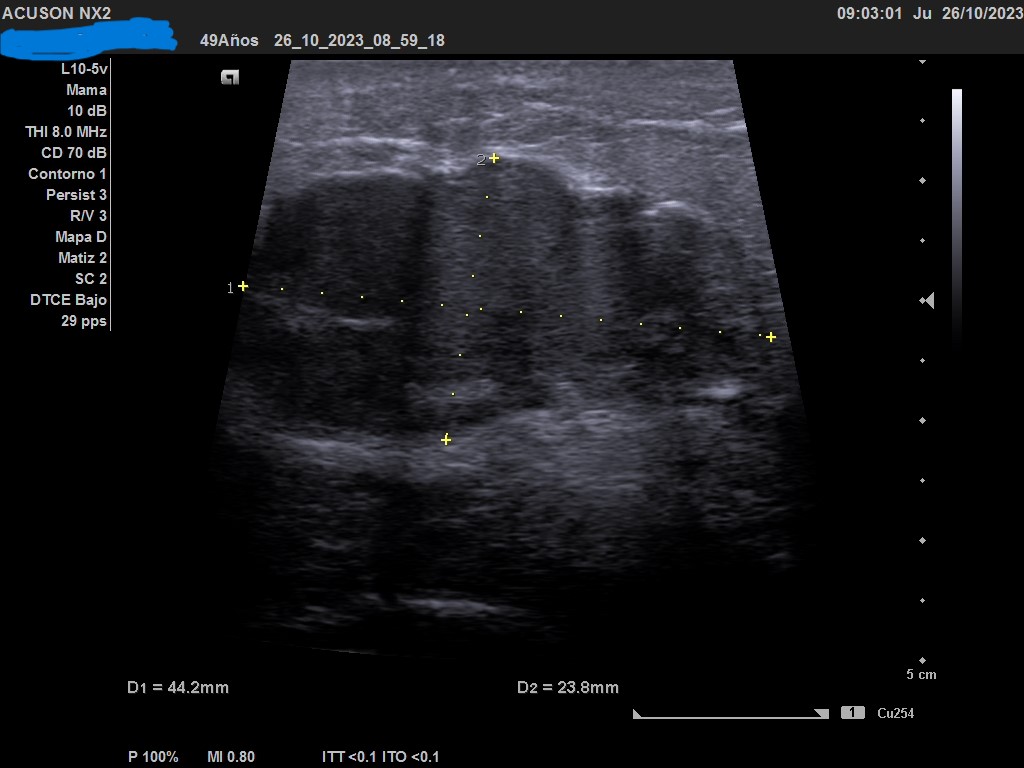

Ecografía: mama izquierda se observa tumoración hipoecogénica lobulada en cuadrante superior externo de aproximadamente 4 cm, heterogénea, que capta al Doppler color y dos adenopatías de aspecto reactivo en axila homolateral. Imagen sospechosa de malignidad.

Ecografía de mama hospitalaria: Se confirma en mama izquierda masa sólida palpable de al menos 56 mm, de contorno mal definido, sospechosa de malignidad. Se realizará BAG ecoguíada, y adenopatías axilares izquierda de aspectos patológico. PAAF de ganglio izquierdo dirigida por ecografía: Citología positiva para malignidad. Compatible con metástasis de carcinoma. Biopsia BA Tipo histológico: Carcinoma infiltrante. Grado histológico: Grado III, pobremente diferenciado.